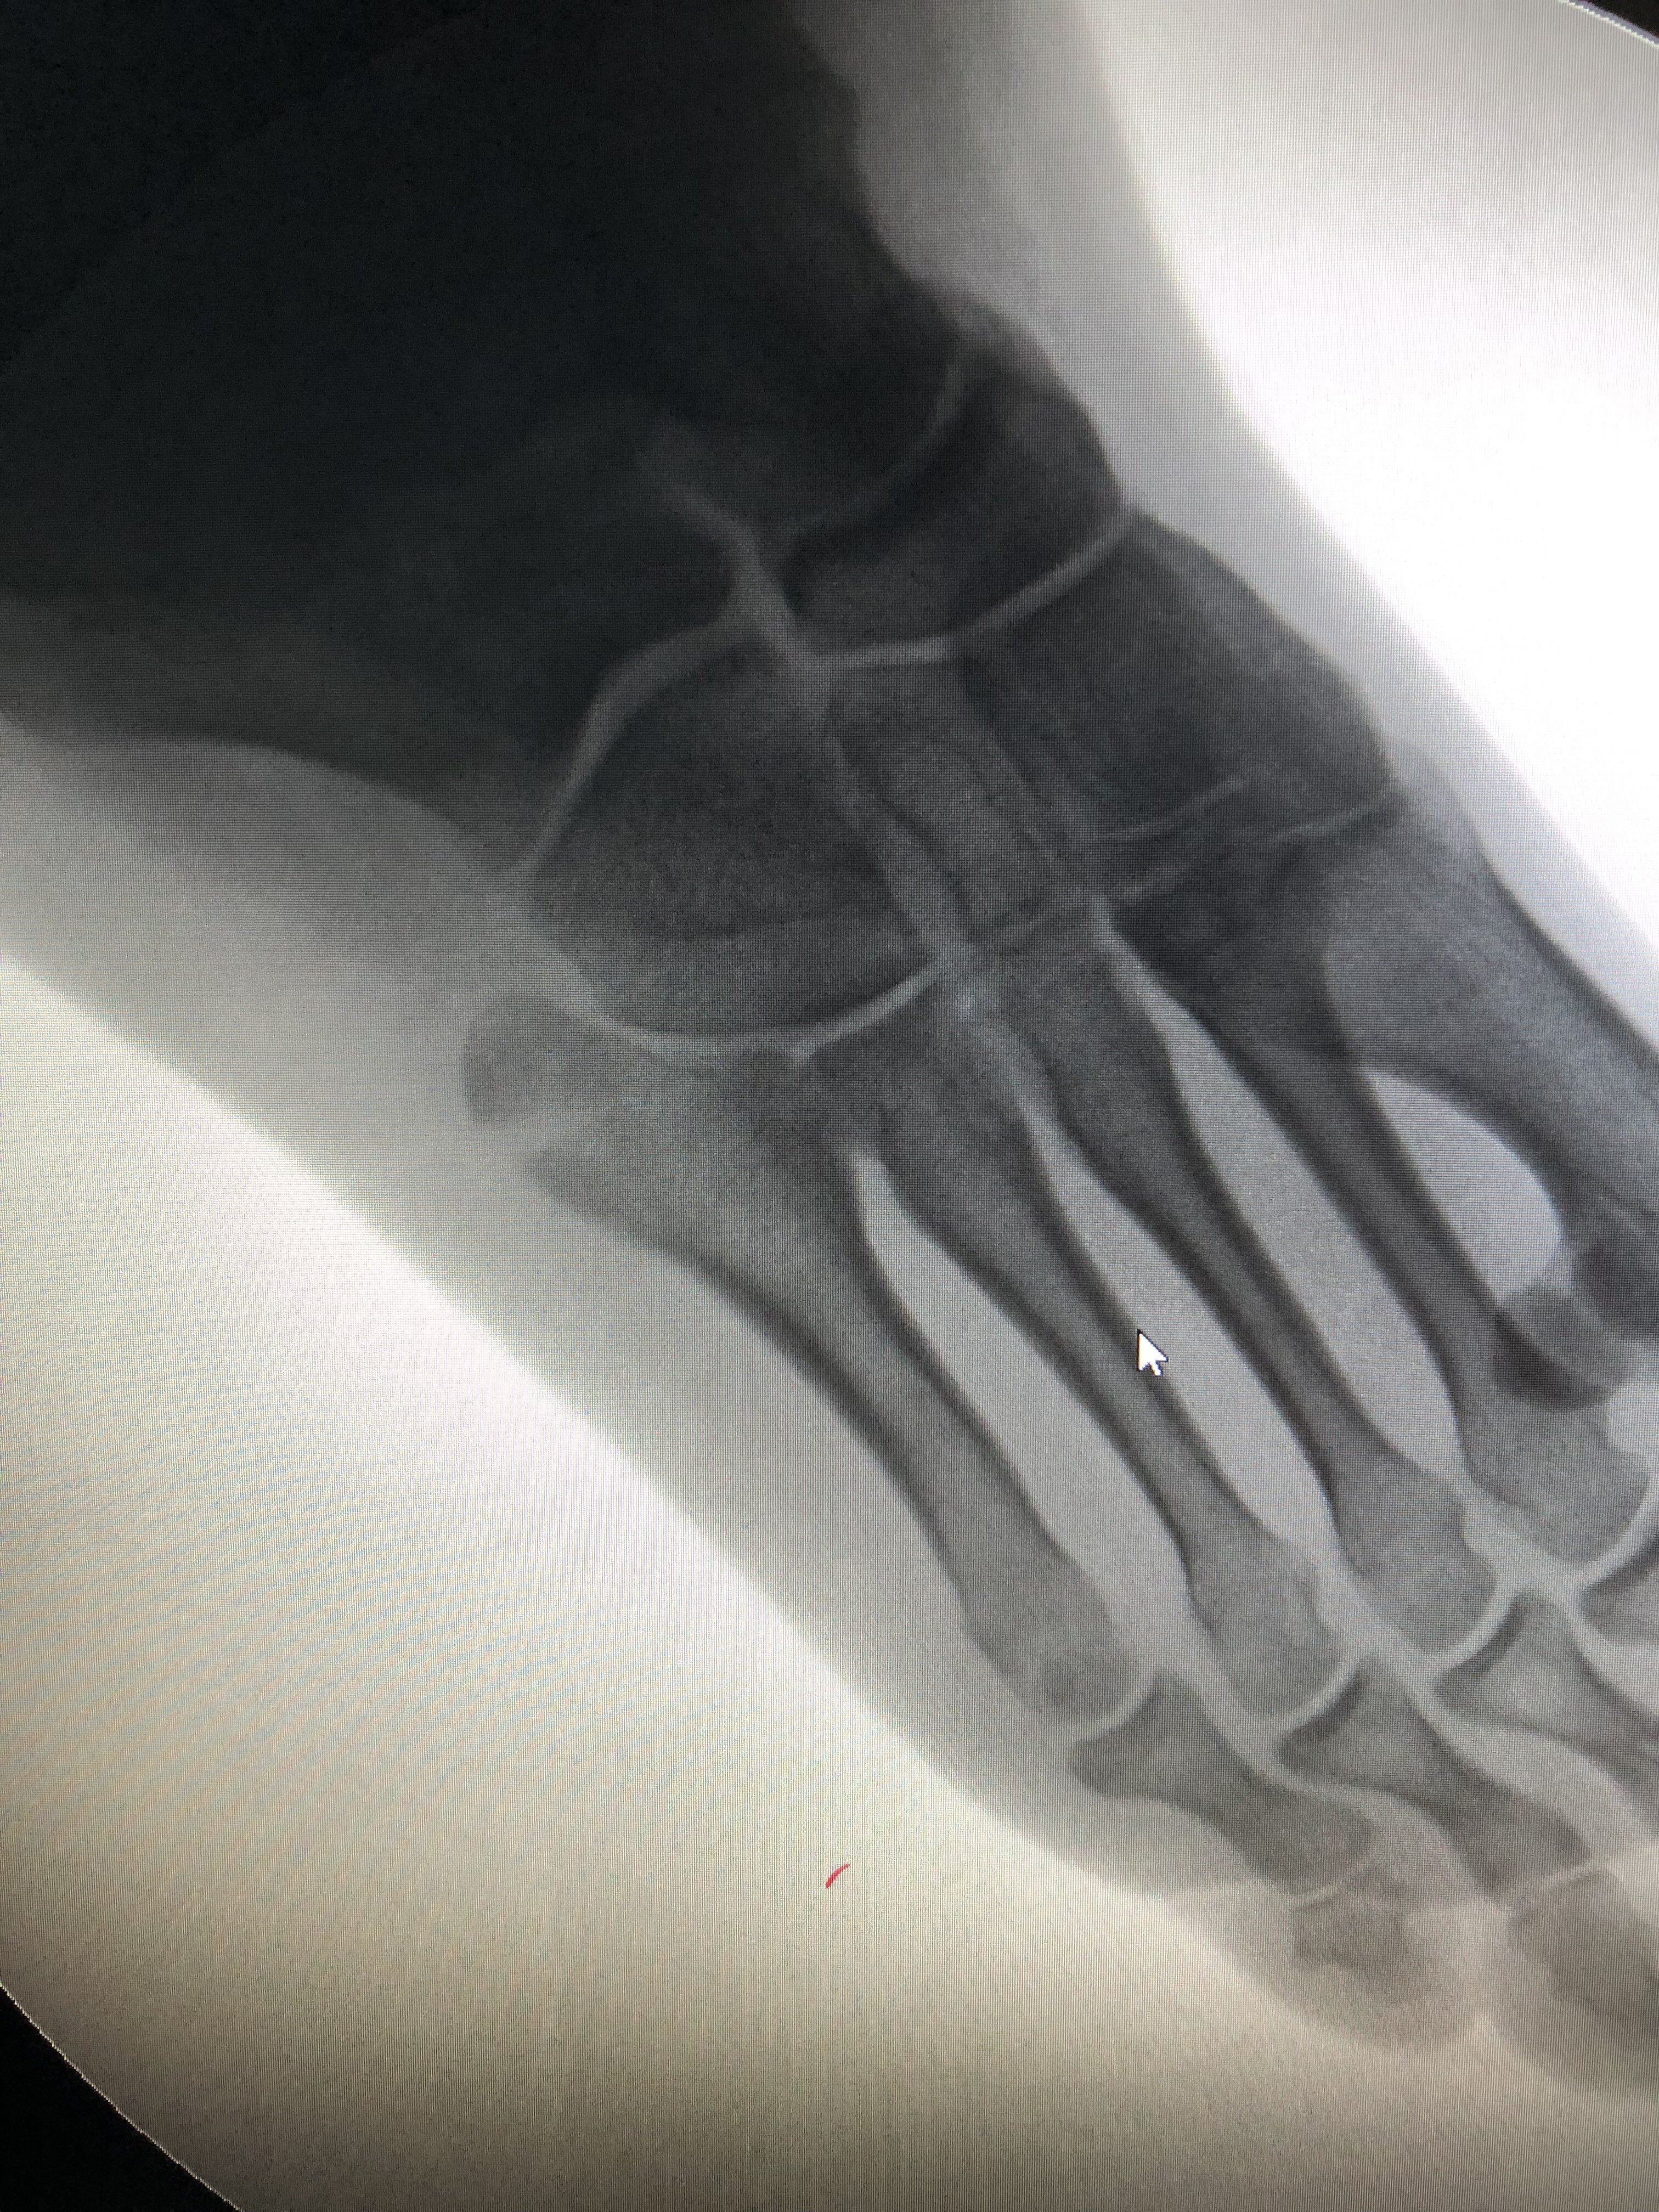

患者提問:疾病:扣扳指病情描述:5.23發(fā)現(xiàn)寶寶左手大拇指一直扣起以為是爬的過程扭啦但是給你揉的時候他沒有啥不舒服的,但是最近幾天發(fā)現(xiàn)那個關節(jié)好像比以前硬啦!想問問是不是那個扣扳指啊!對于他這種小寶寶有啥好的方法治療沒有!然后這個病嚴重不希望提供的幫助:小兒扣板指嚴重不患者提問:可以伸直可以聽到聲音湖北省婦幼保健院骨科明小平回復:家長您好, 從您的描述及結合圖片看,基本可以確定是拇指狹窄性腱鞘炎。 狹窄性腱鞘炎,也稱“扳機指”,一般孩子拇指的指骨間關節(jié)固定在屈曲位,伸直受限。有時可以強迫伸直,但不久又回到屈曲位。被動伸直指間關節(jié)時,有時可聞及彈響,有時孩子會出現(xiàn)疼痛。拇指掌指關節(jié)近端掌側可摸到增粗的肌腱,似一硬結。 早期的話(多指1歲前)可以給孩子拇指按摩,熱敷理療等,可幫助孩子被動活動伸直,一般可聽到拇指伸直彈響聲。若3-6個月后仍無好轉可能,則建議手術治療(小兒骨科小手術,有些地方門診就可以做,效果好,見效快,單側純手術時間約10min)。 目前小兒狹窄性腱鞘炎尚無明確的病因??赡転橄忍煨缘模部赡芾^發(fā)于屈肌腱的后天性結節(jié)狀腫大。一般女孩多見,有出生就發(fā)現(xiàn)的,也有至3歲才偶然發(fā)現(xiàn)的。 通常根據(jù)拇指臨床表現(xiàn)即可診斷,不需要拍X線片。有報道稱新生兒患者中30%,6個月至3歲患者中約12%可自愈。3歲前手術治療,效果滿意。(所以保守無效的話,就要及早手術,最晚不超過3歲,越早效果越好) 手術麻醉問題也不需要過多擔心,因為現(xiàn)在小兒麻醉技術也很成熟,單次、短時間小手術不會對孩子的大腦及發(fā)育產(chǎn)生任何影響。(單次,<3小時是重點,即可理解為“多次手術及超過3小時的手術才可能影響兒童及胎兒大腦發(fā)育”,參考資料來自美國食品藥品監(jiān)管局FDA發(fā)布文章)。所以,考慮手術時也不要過于擔心麻醉問題。